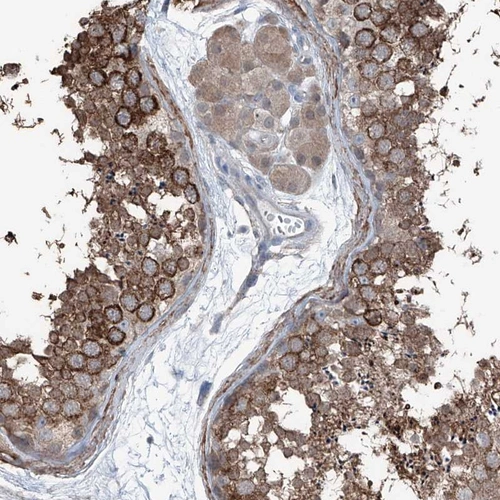

Immunohistochemical staining of human testis shows strong cytoplasmic positivity in cells of seminiferus ducts.